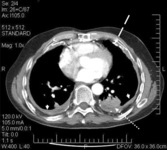

Asbestosis

CT scan of the chest showing multiple examples of pleural thickening most with calcification (arrows)

From the personal collection of Kenneth D. Rosenman MD